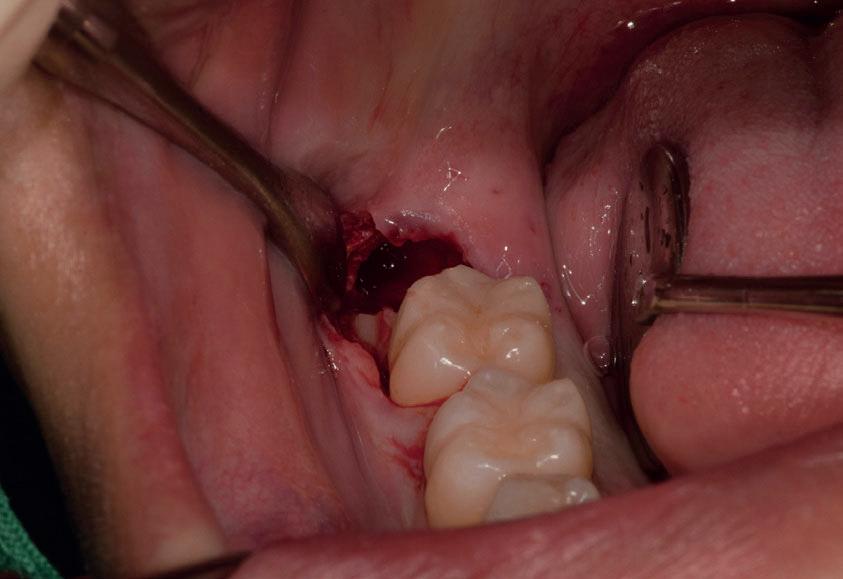

Il seguente caso chirurgico è di un 4.8 mesio-inclinato e parzialmente incluso. Dopo un’incisione a busta, il

dente è stato separato al centro per fare una coronectomia, prima della porzione distale e successivamente della porzione mesiale. Facendo leva quindi è stato possibile rimuovere le radici unite. Figg. 165-172